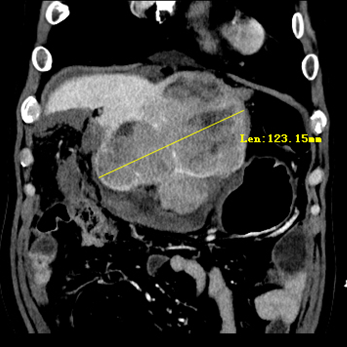

术前影像检查显示肝脏巨大肿瘤

经过一系列检查,苏先生肝脏上的巨大肿瘤考虑为肝癌,凝血功能检测发现凝血酶原时间高达46.3秒,远远高于正常值(14.5秒)。尽管苏先生存在长期慢性肝病,然而肝脏功能和肝储备功能正常,因此凝血功能差不是长期慢性肝病所致,而是先天性凝血因子VII和X缺乏所致。鉴于苏先生病情的特殊性,我院副院长、肝脏外科学科带头人杨扬教授、肝脏外科主任李华主任医师和肝脏外科二区主任张剑主任医师迅速组织了学科病例讨论和全院多学科会诊。经过肝脏外科、血液内科、输血科、外科ICU和手术麻醉中心等学科讨论,认为苏先生肝癌手术指征明确,先天性凝血因子VII和X缺乏会导致内源性和外源性凝血途径障碍,术中出血风险较大,要严密监测凝血状态,以较小的创伤和较短的时间完成手术,需要熟练的肝脏外科手术技术和多学科团队的默契配合。